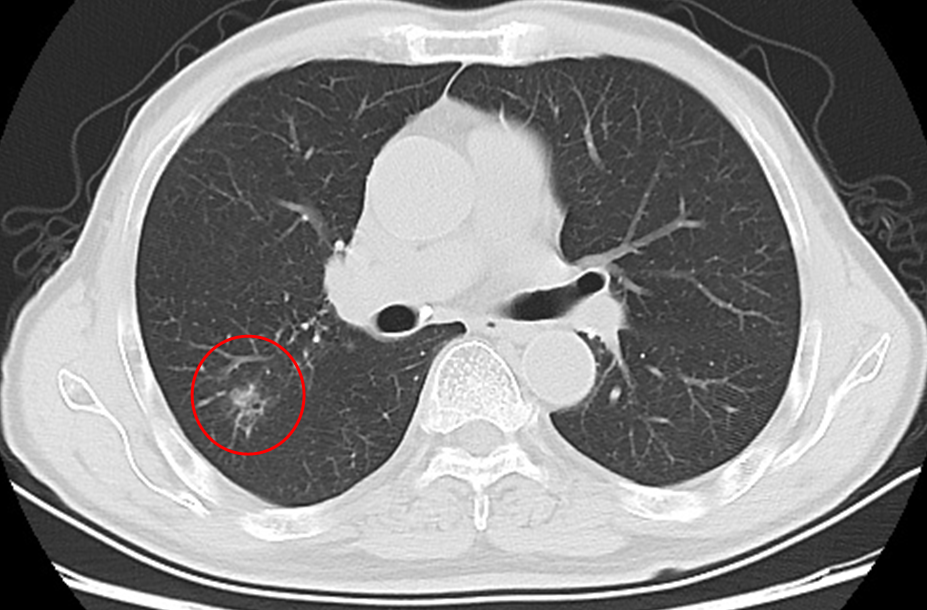

△胸部CT提示右肺上叶后段直径约18mm亚实性结节,边缘不规则

从影像学角度来看,如果不能明确是良性的,结节越大恶性的可能性越大;结节具有恶性征象,如有分叶、毛刺、胸膜牵拉、含气细支气管征和小泡征、偏心厚壁空洞等,倾向于恶性;随访过程中,结节增大或实性成分增多,倾向于恶性。